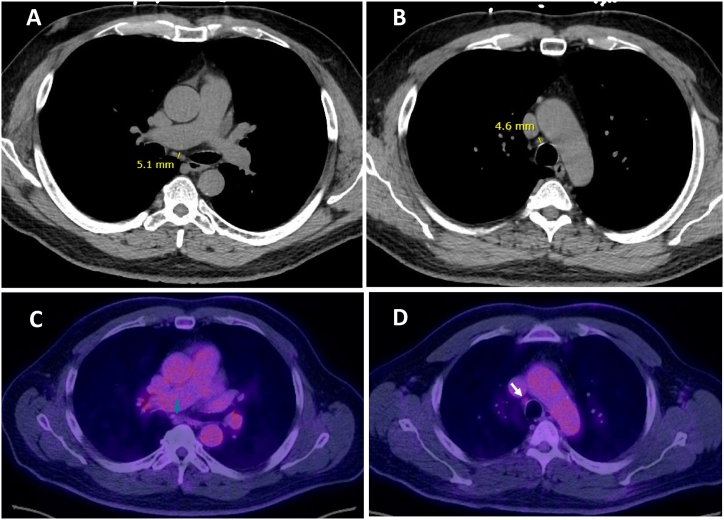

结节病是一种罕见的慢性肉芽肿性疾病,病因不明。心脏结节病(CS)的明确诊断尤其困难。有几种诊断CS的指南,但尚未得到临床验证。尽管心肌膜活检具有高特异性,但其敏感性低,潜在并发症的严重程度高。因此,我们报告63岁男性,经支气管超声(EBUS)经支气管针吸(TBNA)胸内淋巴结诊断为CS,该淋巴结未扩大,无PET可见性。影像学上表现正常的淋巴结EBUS - TBNA显示非坏死性肉芽肿。鉴于CS诊断的挑战,即使在没有明显活动性肺结节病证据的病例中,也可以考虑EBUS TBNA。

Sarcoidosis is a rare chronic granulomatous disease with unknown etiology. Definite diagnosis of cardiac sarcoidosis (CS) is especially difficult to establish. Several guidelines exist to make a diagnosis of CS but those have not been clinically validated. Despite the high specificity of endomyocardial biopsy, its sensitivity is low, and the severity of potential complications is high. Thus, we present 63-year-old male who was diagnosed with CS with the endobronchial ultrasound (EBUS) transbronchial needle aspiration (TBNA) of intrathoracic lymph nodes which were non-enlarged without PET avidity. EBUS TBNA of radiographically normal appearing lymph nodes showed non-necrotizing granulomas. Given challenges of diagnosing CS, EBUS TBNA can be considered even in cases without obvious evidence of active pulmonary sarcoidosis.